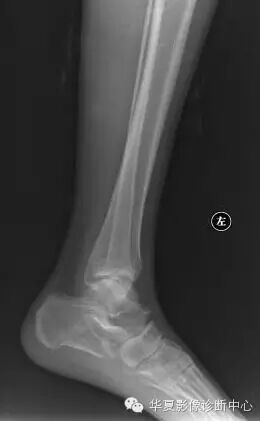

距骨嘴为距骨发育变异,常易被误诊为骨质增生及肿瘤。可引发一系列临床症状:不明原因的踝部“酸痛”,行走、站立常出现踝部酸胀感,时久甚之为主要症状。

主要体征:踝部软组织轻度肿胀、压痛,踝关节背屈、跖屈运动稍受限并症状有加重。可通过矫形外科治疗,切除后为正常骨性结构。

X线征象具有一定的特征性:

1、整个距骨形态呈“鸟头”状。

2、距骨颈短甚至消失。

3、“鸟头”具有一呈三角状向前突出的“鸟嘴”并具有正常的骨结构。

4、距骨头部与舟状骨关节接触面变小而呈圆弧性。